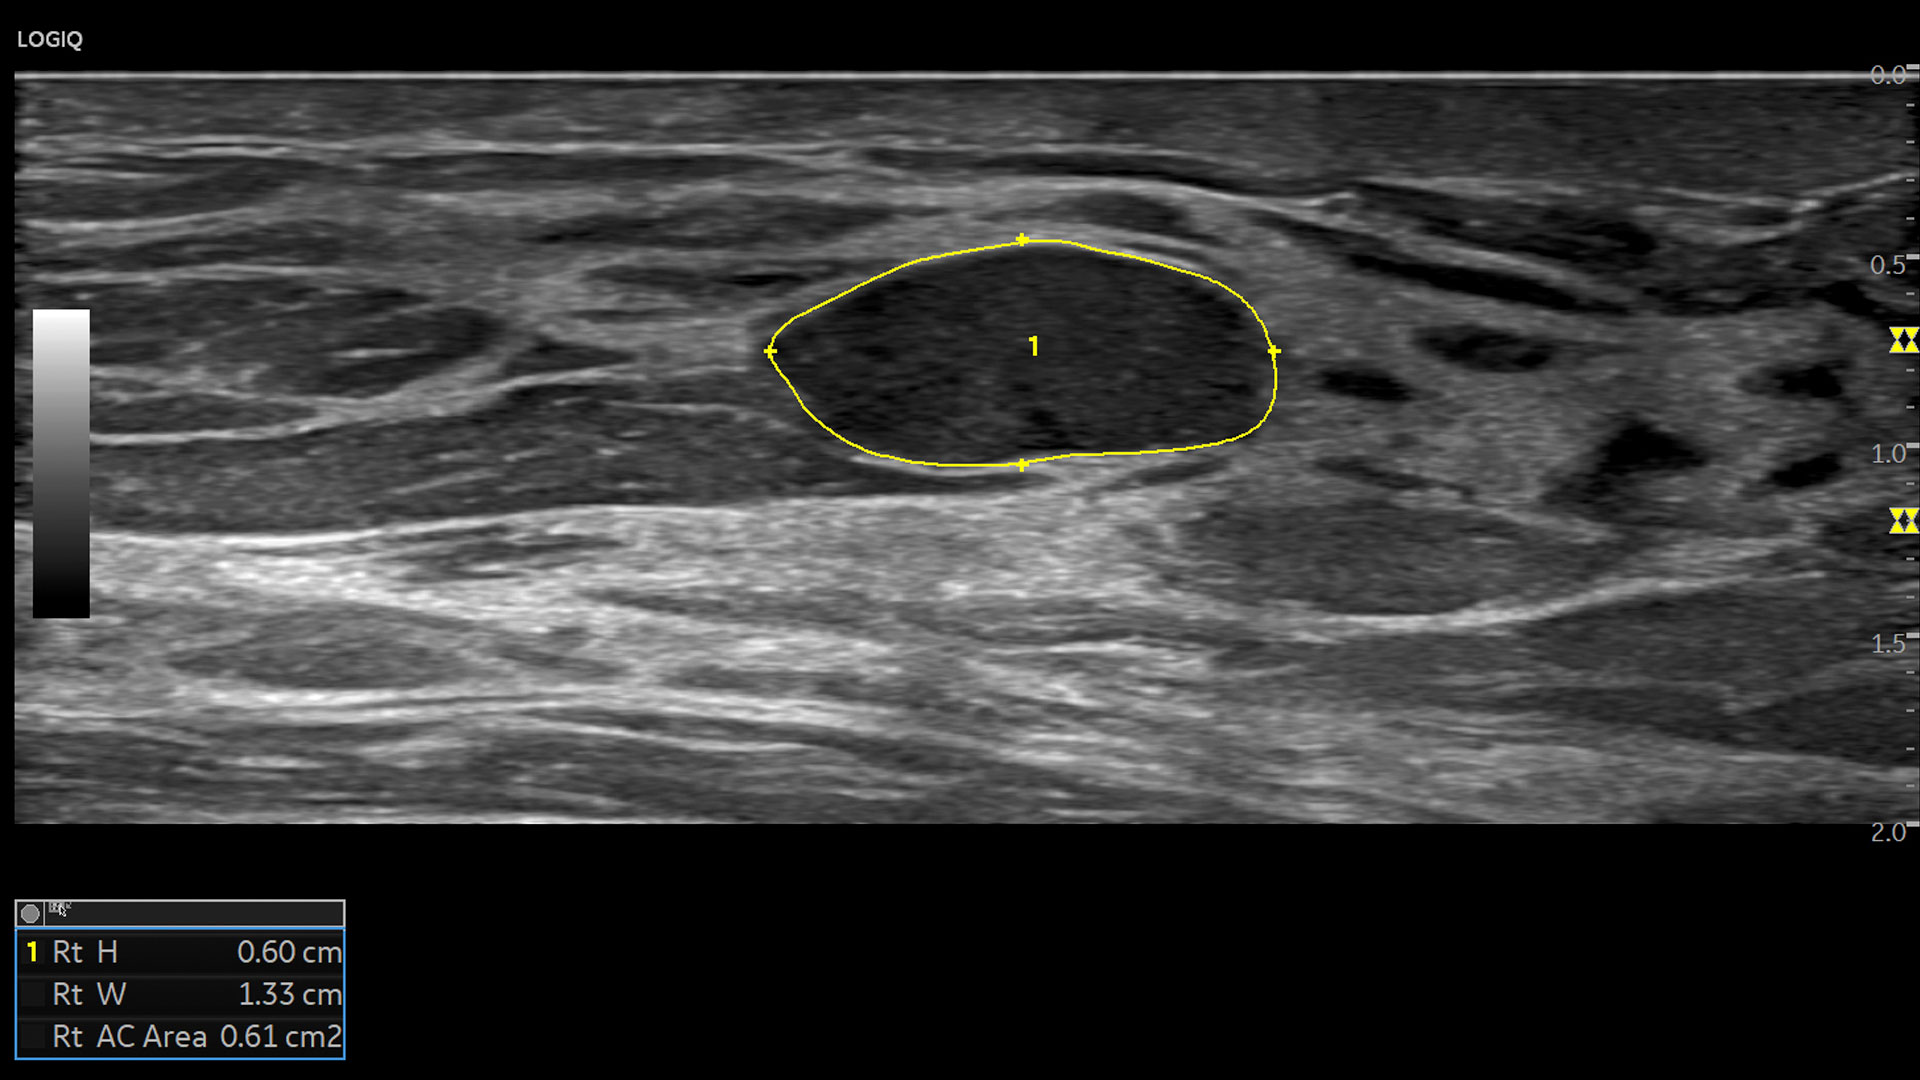

Multi-purpose capabilities, including liver, cardiac, OB/GYN, vascular, breast, thyroid, musculoskeletal, urologic, and pediatric studies.

Superb image quality with XDclear probes: Powerful high fidelity and broad bandwidth produce high resolution images whether scanning superficial or deep targets.